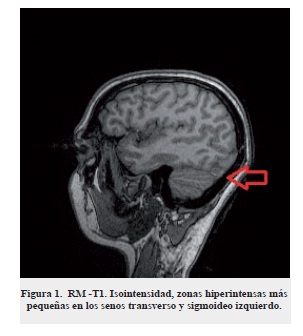

La paciente fue referida a la Fundación Centro Colombiano de Epilepsia y Enfermedades Neurológicas-FIRE por presentar cefalea occipital pulsátil de intensidad moderada de un mes de evolución asociado con náuseas, emesis, fotofobia, sonofobia, sin antecedentes de trauma craneoencefálico, ni enfermedades autoinmunes, sin historia de amenorrea, tampoco de abortos (G 0 P0 A0). A la evaluación física se observó en regular estado músculo nutricional, con signos vitales en metas FC: 82 latidos por minuto, FR: 18 respiraciones por minuto, normotensa con una presión arterial de 110/60 mm Hg, temperatura: 36,5 grados centígrados, peso 46 kg. El examen neurológico es normal sin presencia de signos patológicos. Como diagnóstico inicial se consideró el diagnóstico cefalea con signos de alarma. Se le ordenó una resonancia magnética cerebral (RM) 1,5 tesla que mostró una trombosis aguda del seno transverso y sigmoideo izquierdo (figura 1,2) punción lumbar con presión de apertura elevada. La prueba de embarazo fue negativa, hemograma con anemia leve, normocítica, normocrómicas, leucocitosis 16.490 mm3, sin trombocitos, nitrógeno ureico, creatinina, glucemia, tiempos de coagulación, proteinograma normales. Se inició anticoagulación con enoxaparina, previamente se realizaron paraclínicos de extensión para determinar causa de trombosis venosa cerebral, reportando proteína S por ELISA disminuida; factor V de Leiden, proteína C, antitrombina III y factor VIII normal, siklemia negativa, anticoagulante lúpico negativo, anticardiolipinas IgG e IgM negativa, anticuerpos antinucleares negativos; panangiografía cerebral comprueba trombosis del seno transverso y sigmoideo izquierdo (figura 3). Posterior al tratamiento, la paciente inició mejoría gradual a su estado, a los 14 días de estancia hospitalaria fue enviada a su casa con anticoagulación ambulatoria con enoxaparina subcutánea por 2 semanas y luego manejo con anticoagulación oral.

Para el diagnóstico de TSVC se debe partir de una minuciosa evaluación clínica y sospechar cuando se está ante la presencia de síntomas como cefalea, vómito o nauseas, signos de hipertensión endocraneana, papiledema, estados de hipercoagulabilidad, embarazo, puerperio o utilización de anticonceptivos hormonales19. En el caso de las ayudas diagnósticas, la utilización de la resonancia magnética nuclear permite ver con mayor facilidad la oclusión del seno venoso20.